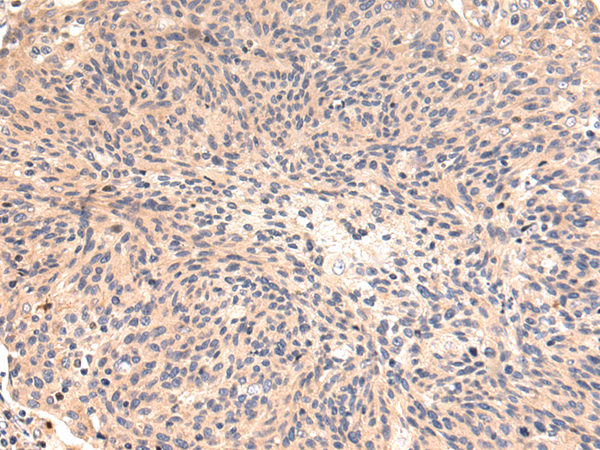

分类: 科研抗体货号: P08418别名: I; HSD3B; HSDB3; HSDB3A; SDR11E1; 3BETAHSD应用: WB,IHC反应种属: Human